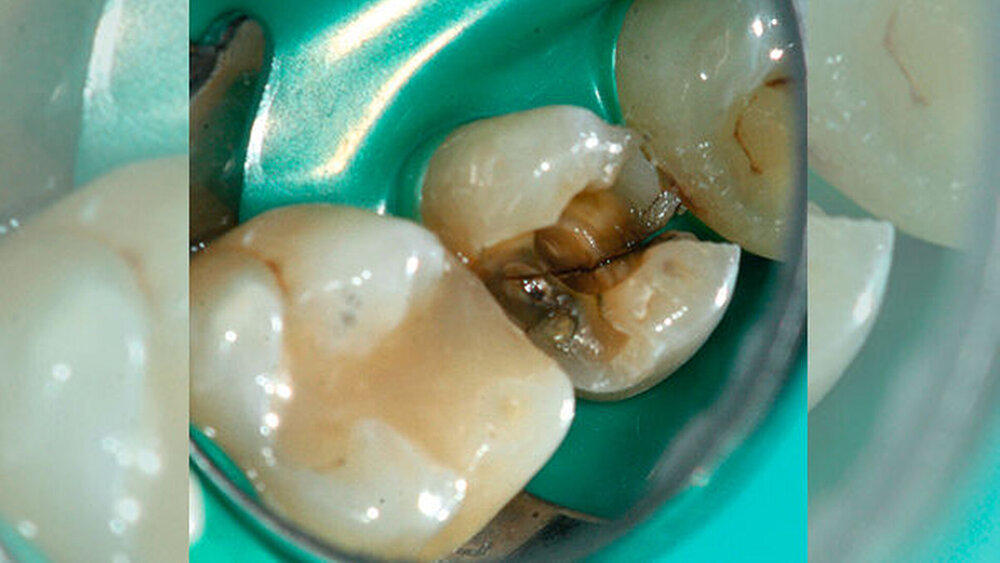

Eine 54-jährige Patientin wurde aufgrund einer Längsfraktur, die während einer Wurzelkanalbehandlung im Rahmen eines Studentenkurses und derzeitiger medikamentöser Einlage an Zahn 15 eintrat, in der Poliklinik für Zahnerhaltung des Universitätsklinikums Münster vorstellig. Während die allgemeinmedizinische Anamnese unauffällig war, zeigte sich klinisch nach Entfernung der vorhandenen mod-Glasionomerzementfüllung ein deutlicher Frakturspalt in mesial- distaler Ausrichtung am Boden der Kavität (Abbildung 1). Darüber hinaus war auf der Röntgenaufnahme des Vorbehandlers eine apikale Aufhellung zu erkennen (Abbildung 2).